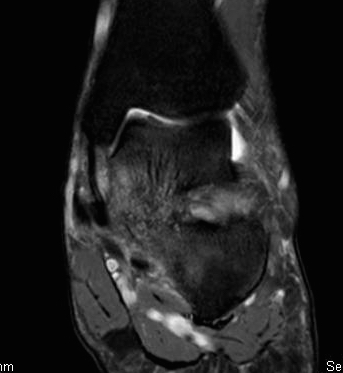

MRI

TC coalition middle facet